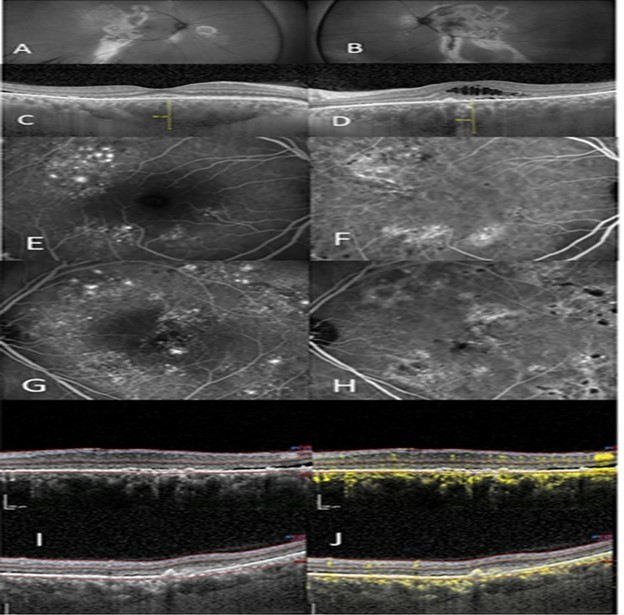

Figure 2.(A) right eye show autofluorescent discontinuity with peripheral tracks. (B) left eye show similar changes however central changes are present. (C), (D) OCT/EDI shows pachychoroid, pachy vessels, varying degrees of subretinal and intraretinal fluid, right eye (C), left eye (D). (E) IVFA right eye shows non-specific extrafoveal occult leakage. (F) ICG right eye with ICG hyperfluorescence and corresponding leakage. (G) IVFA leakage, left eye with several focal leaks amongst wider areas of non-focal leakage. (H) ICG shows diffuse hyperfluorescence corresponding to IVFA leakage. (I) OCT shows two images of the left macula with the “double layer sign” superior and a visible Type 2 neovascular membrane inferior, thickened choroid, and subretinal fluid and (J) with corresponding OCTA scans showing neovascularization.

Figure 2 outlines a 52 year old Latino male, previously treated unsuccessfully with eplerenone (Inspra) and multiple anti-VEGF injections in both eyes. He was referred with the diagnosis of Exudative ARMD with a possible CSCR component due to his gender and age. He had chronic exudation, left eye greater than right eye, with macular atrophy left eye and subsequent vision loss. Autofluorescence of each eye reveal prominent peripheral discontinuity with classic gravitational tracks. Additionally, central changes are present in the left eye consistent with the macular atrophy and vision loss. IVFA of both eyes showed widespread extrafoveal exudation with areas of non-specific occult leakage as well as focal leaks. ICG hyperfluorescence shows diffuse choroidal leakage in both eyes. OCT showed a thickened choroid and pachyvessels with the OCTA revealing areas of “double-layer” sign. This patient had simultaneous Group 1 and Group 2a diagnoses.